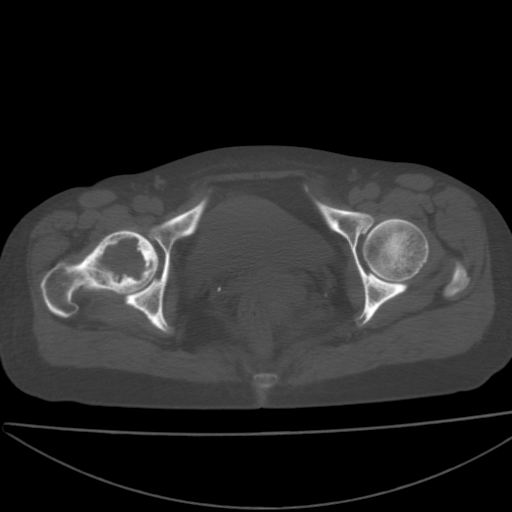

以下是引用xiaoniu在2008-9-6 8:22:00的发言:[br]右侧股骨颈囊性低密度,囊壁边缘硬化,中年妇女,首先考虑:骨囊肿。其次考虑动脉瘤样骨囊肿。[br][br][br][本贴已被 xiaoniu 于 2008-9-6 9:04:54 修改过]